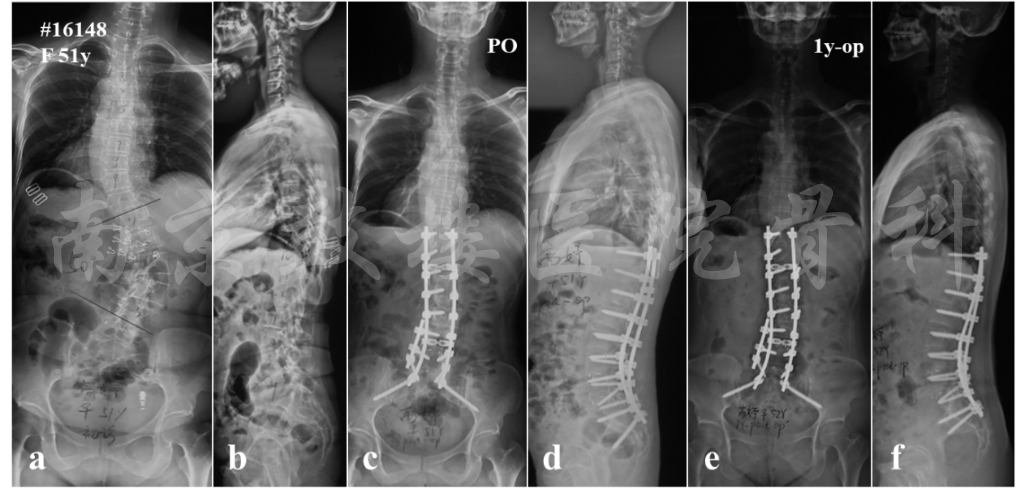

图6 女,51岁。X片示冠状面Cobb角50°,矢状面无明显失平衡或腰椎后凸(a, b),因此无需进行三柱截骨,行后路T10-S2内固定,L4/5、L5/S1 TLIF(c, d),术后1年,内固定在位,融合好,冠矢状面平衡保持良好(e, f)